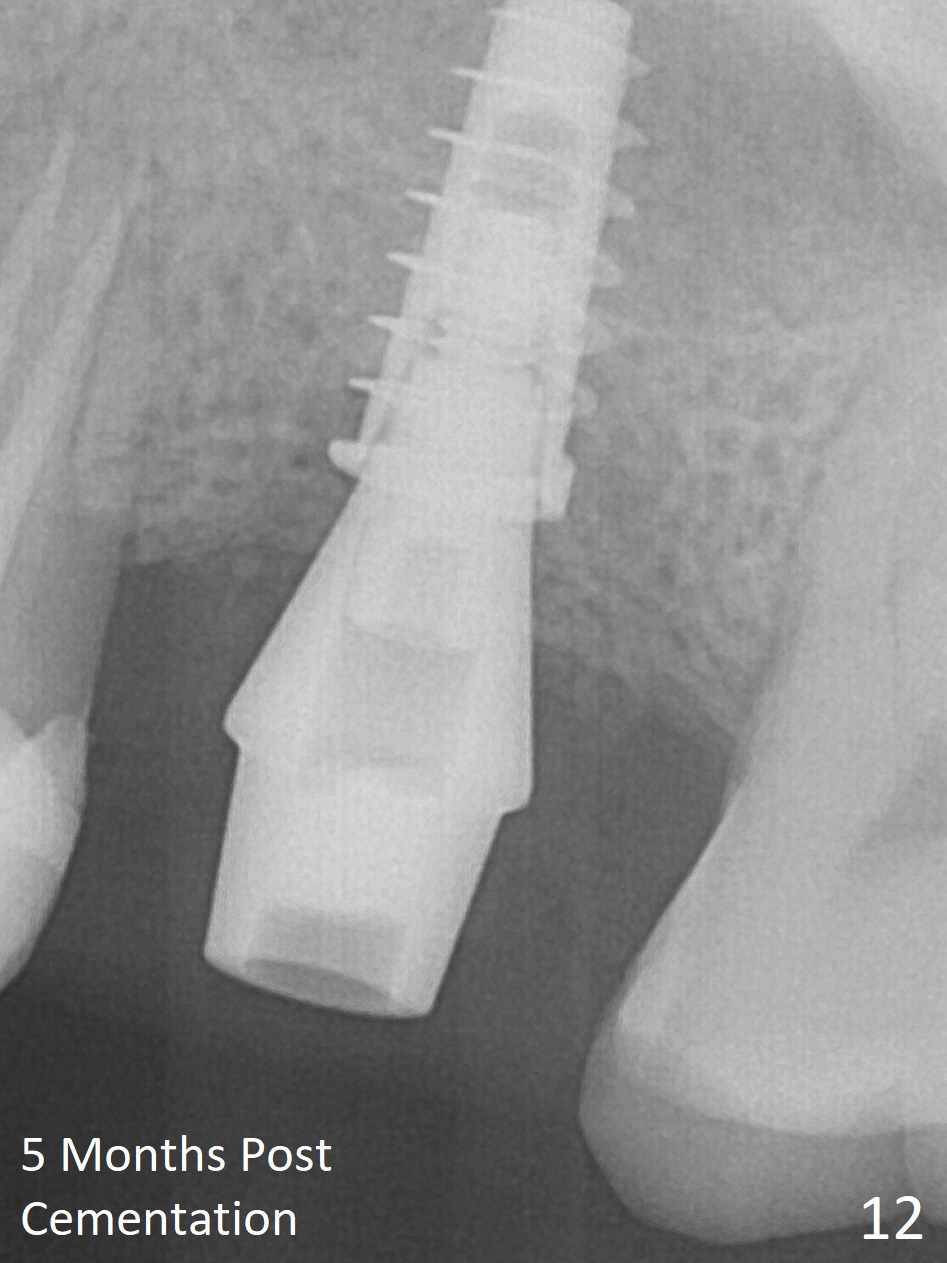

After extraction of the distobuccal residual root of the tooth #14 (Fig.1 arrow), the gingiva around the socket does not look like the keratinized one (Fig.2 *). An osteotomy through the distobuccal socket would seem too buccal for immediate implant. The palatal gingiva feels too tough to be stretched. An incision is made (Fig.3 dashed line); with elevation, the thick flap is transferred buccally (curved arrow). An osteotomy is initiated in the palatal bone with 1.5 mm drill, followed by Magic Expanders until 4.3 mm for 11 mm (Fig.4,5). Following Magic Drill 3.8x13 mm, the sinus membrane is found to be perforated. The latter is repaired with Osteogen plug. A 4.5x9 mm IBS implant is placed with 50 Ncm (Fig.6). Osteogen plug and allograft (Fig.7 *) are inserted into the remaining distobuccal socket (reduced after bone expansion). When a 5.5x4(4) mm abutment is placed, the transferred flap appears to be adapted to the distobuccal defect (Fig.8 *). Later one suture is placed for fixation. After provisional insertion, periodontal dressing is applied. Nine days postop, the periodontal dressing dislodges. When the loose provisional is removed for recementation, the flap seem to have healed (Fig.9 *). The gingiva heals around the abutment 5 months postop (Fig.9); the distal socket appears to heal while the bone graft remains at the crest (Fig.11,12). When #30 develops buccal abscess, the patient masticates on the left, leading to loss of composite at #13 (Fig.14); in fact the abutment at #14 is incompletely seated.